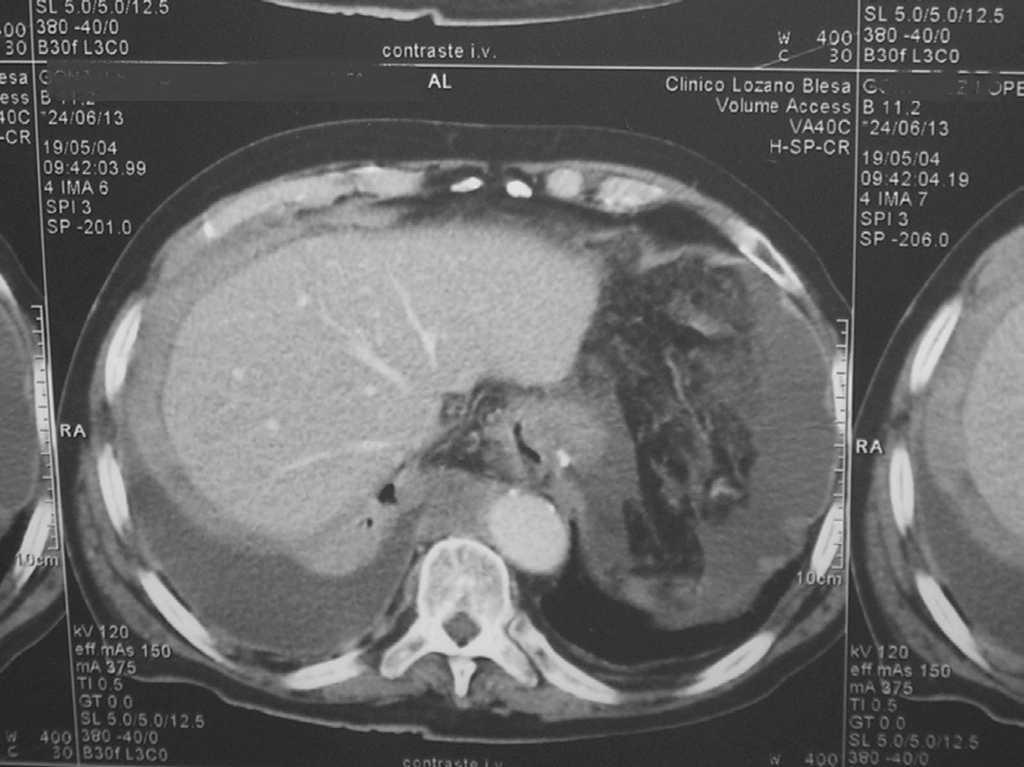

Ante los hallazgos físicos y analíticos comentados, se decidió realizar una tomografía computarizada (TC) toracoabdominal, que mostró un parénquima pulmonar colapsado por derrame pleural parcialmente encapsulado, con engrosamiento de pleura parietal de hasta 15 mm que parecía infiltrar la pared torácica, y abundante líquido ascítico tabicado con aumento de densidad en epiplón y peritoneo parietal (figs.1 y 2).

Figura 2.TC Toracoabdominal.

La TC toracoabdominal orientó el diagnóstico hacia un mesotelioma --neoplasia muy poco frecuente en su localización abdominal, muy relacionada con el asbesto9--, sin descartar adenocarcinoma pleural metastásico. El antecedente del contacto con asbesto no se pudo comprobar en la historia de nuestro paciente. En diversos estudios se ha observado un elevado porcentaje de casos sin historia de exposición a asbesto, como el estudio mexicano que no lo demostró en un 80% de 45 casos de mesotelioma maligno10,11.

La sospecha clínica de mesotelioma estaba justificada en este paciente, ya que el mesotelioma maligno es la tumoración maligna primaria más frecuente de la pleura12, y su manifestación más frecuente es el dolor torácico seguido de disnea; las alteraciones radiológicas más frecuentes son el derrame pleural generalmente unilateral y la masa o engrosamiento pleural. En el mesotelioma peritoneal es la ascitis, signo también presente en nuestro enfermo.